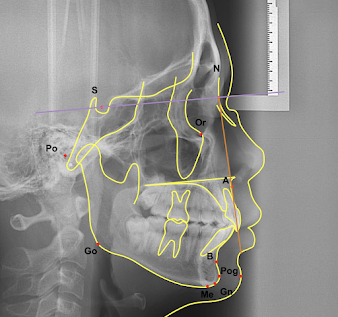

Analisis sefalometri dapat dilakukan melalui berbagai teknik, seperti analisis Steiner, Tweed, dan Wylie. Namun semua analisa ini diawal dengan hal yang sama. Hal pertama yang perlu dilakukan untuk menganalisa hasil sefalometri adalah menentukan titik landmark pada cephalogram. Beberapa landmark itu diantaranya:

- S = Titik tengah dari sella tursica

- N = Titik paling anterior pada sutura frontonasal.

- Or = Titik paling inferior pada lengkung orbita.

- A = Titik pada kurvatura tulang alveolar terdalam rahang atas.

- B = Titik terdalam pada kontur anterior simfisis mandibula.

- Pog = Titik paling anterior dari tulang dagu.

- Gn = Titik paling anteroinferior dari tulang dagu (diantara Pog dan Me).

- Me = Titik paling inferior dari simfisis mandibula.

- Go = Titik paling posteroinferior dari sudut mandibula.

- Po = Titik paling superior dari external auditory meatus.